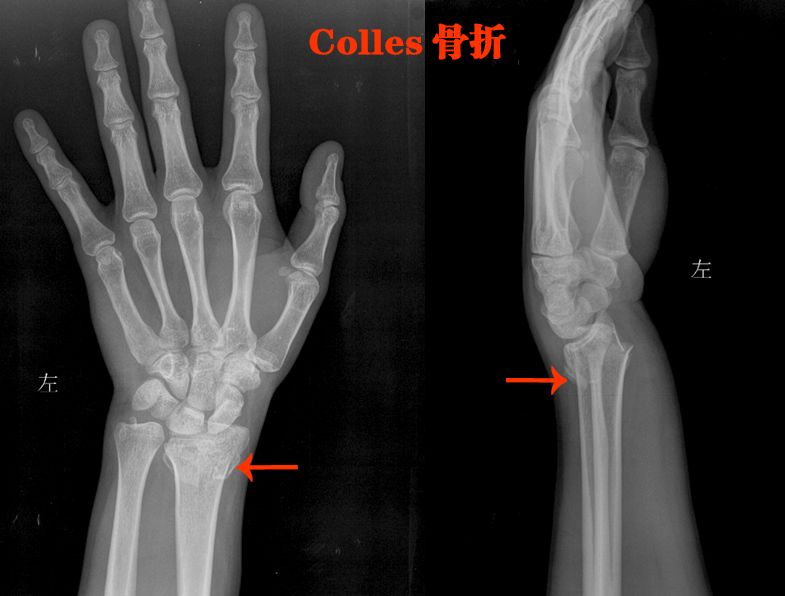

四、长骨骨折

就是四肢的长骨骨折

上肢:

肱骨、尺骨、桡骨

下肢:

股骨、股骨头、胫骨、腓骨

骨折非常简单的

这里就不讲解了,大家看片就行

看片